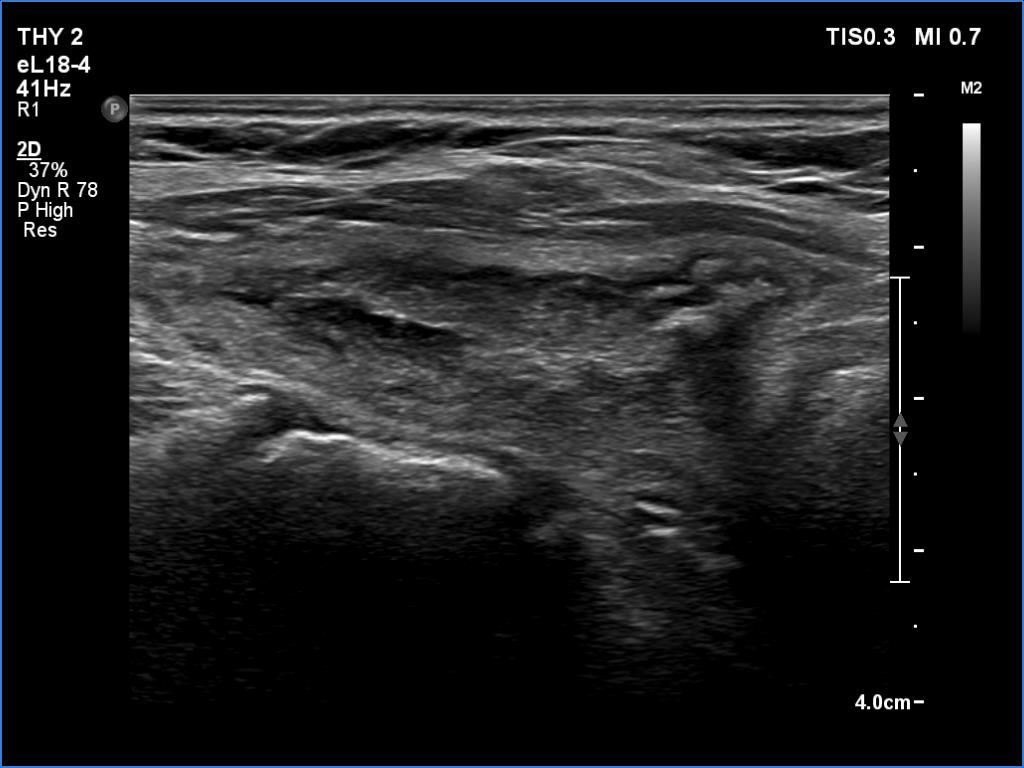

Ultrasonography. The thyroid was echonormal. There were several hypoechoic areas in the right lobe. The left lobe had a large minimally hypoechoic nodule with several tiny cystic areas. The lesion had numerous back wall figures.

14 mL thick yellow fluid was aspirated. Cytology resulted in cystic fluid only, Bethesda I category.

This case illustrates two rare phenomena. On the one hand, a dense liquid may appear to be a solid tissue. On the other hand, the Doppler assay actually detects fluid flow. In the vast majority of cases, of course, this displays a circulation in the blood vessels, but in the case of cysts, when pressure is applied to the fluid with the probe, a flow is created. In the case of flow in blood vessels, circulation is always seen in the same place, while in the case of flowing cystic fluid, the flow can be detected in constantly changing places.